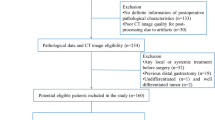

Pre-NAC clinical and imaging data of AEG patients who underwent surgical resection after preoperative-NAC at two centers were retrospectively collected from November 2014 to September 2020. The dataset included training (n = 60) and external validation groups (n = 32). Three models, including CT-based radiomics, clinical and radiomics–clinical combined models, were established to differentiate pCR (tumor regression grade (TRG) = grade 0) and nonpCR (TRG = grade 1–3) patients. For the radiomics model, tumor-region-based radiomics features in the arterial and venous phases were extracted and selected. The naïve Bayes classifier was used to establish arterial- and venous-phase radiomics models. The selected candidate clinical factors were used to establish a clinical model, which was further incorporated into the radiomics–clinical combined model. ROC analysis, calibration and decision curves were used to assess the model performance.

Clinical, pathological and CT imaging data of AEG patients who underwent surgical resection after preoperative NAC at the First Affiliated Hospital of Zhengzhou University and Henan Provincial Cancer Hospital were retrospectively collected from November 2014 to September 2020. The patient enrollment criteria included the following: (1) AEG confirmation by gastroscopic biopsy pathology prior to treatment; (2) pre-NAC clinical stage of cT2–4N0–3M0 stage; (3) NAC treatment in 2–6 cycles; (4) lack of other antitumor therapy administered before NAC; (5) enhanced CT scan obtained within 1 week prior to NAC treatment with complete imaging data; (6) lesion covering at least 3 slices on CT cross section and a maximum plane diameter of at least 2 cm; and (7) radical resection performed after NAC treatment with complete postoperative pathology data. The exclusion criteria included: (1) combined history of other malignancies; (2) poor CT image quality or lack of raw DICOM data; (3) adverse event during NAC or less than 2 cycles of NAC; (4) combined heart, lung and other important organ dysfunction in which a CT examination could not be performed; and (5) incomplete CT imaging data or clinical and pathological data.

Patients with AEG from the First Affiliated Hospital of Zhengzhou University were included in this study as the training group (n = 60), and 32 patients with AEG from Cancer Hospital of Zhengzhou University were included as the external validation group (n = 32).